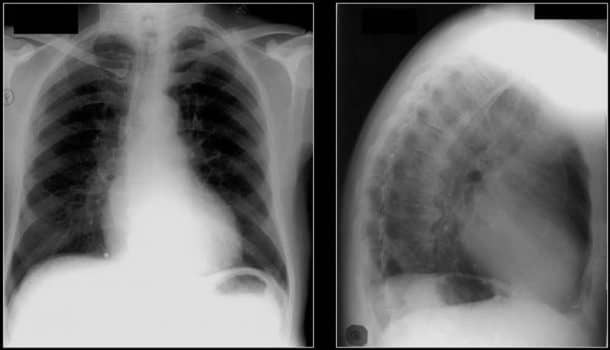

最不为人知的发明之一是Thorotrast,这是一种于1931年推出的x射线造影剂。虽然它的用途是正确的,但它具有相当大的放射性。你可以想象它对受感染的病人的影响。它有近22年的半衰期,在肝脏、脾脏和骨骼中积累。它只延迟了20到30年,就导致了患者的肝癌和白血病。它的致癌作用此前并不为人所知。不幸的是,很多病人甚至不知道他们随身携带的定时炸弹。

胸部x光片显示后纵隔淋巴结有胸隔物沉积。